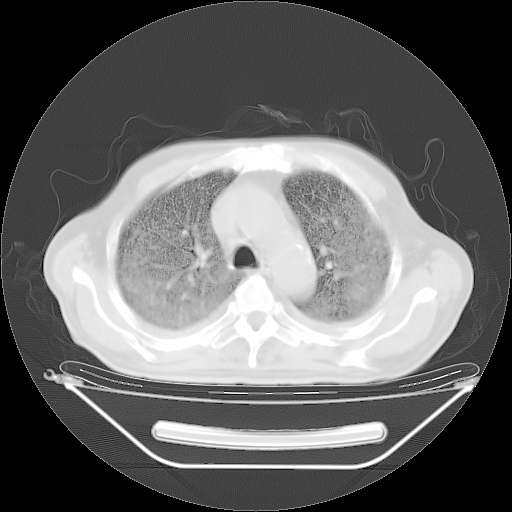

胸腹部CT,诊断意见:左上肺叶钙化灶、左侧胸膜局限性增厚并钙化、胆囊炎。描述部分肺组织呈磨玻璃样改变。

今天复查肺部CT,发现双肺广泛磨玻璃样改变。所以我把3月19日和5月9日相隔50天的肺部CT上传。请大家会诊。

2009年3月19日肺部CT片。

2009年3月19日肺部CT

大致读了系列胸部CT:纵隔窗无明显异常,肺窗:从4、27至今:主要是双肺中下野外带可见毛玻璃样改变,目前处于急性肺泡炎阶段,至于原因考虑1、结替组织或胶原血管性疾病所致?2、恶性疾病如恶组在肺部所致的表现或细支气管肺泡癌?3、药物或其它原因如肺蛋白沉着症所致肺泡炎目前不太可能?总之,明天就去请我院的呼吸科、感染科、血液科和临免专家会诊哈。